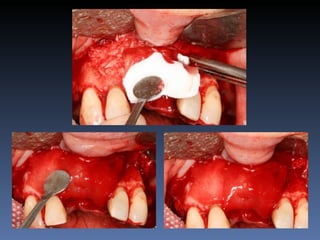

Silvia Maria Cardoso

Diagnóstico: Desdentada pré-maxila

Plano de tratamento:        Reabilitação com 2 blocos

“onlay” provenientes de Ilíaco fresco-congelado

(FFB); e posterior reabilitação protética fixa .

Leito nativo atrófico

Preparação e modelação dos blocos

Descorticalização do leito receptor

Fixação dos blocos “ onlay “

Mensuração pós fixação:

Pré - 1,0 mm

Pós – 5,5 mm